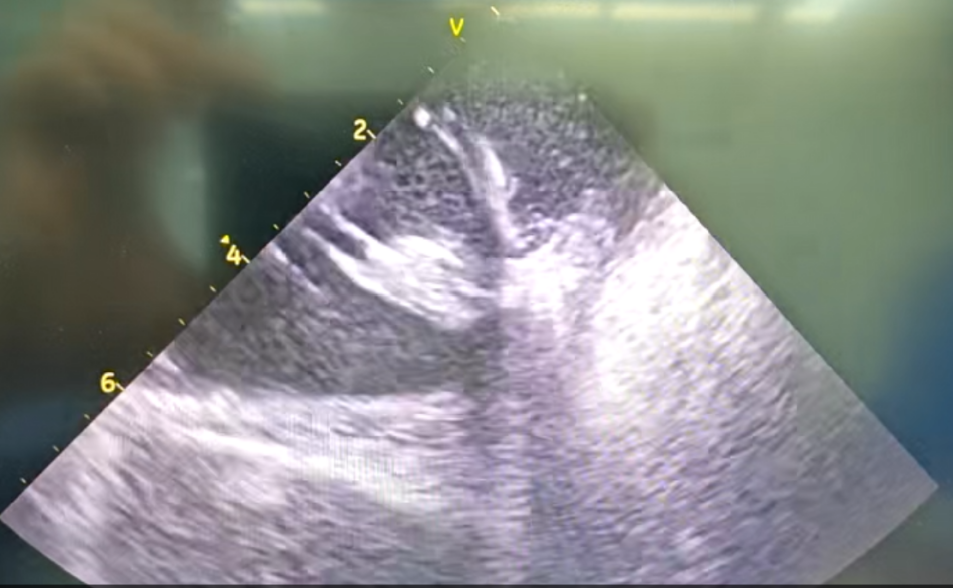

部分内膜室速靶点电位

王林林主任医师谨慎操作,成功进入心外膜达到病变位置。术中,患者反复自发多形态室速,且转为室扑,同时出现血流动力学不稳定,需多次电除颤方能终止发作,标测难度极大。这就要求医疗团队必须在有限的标测时间内精准定位室速消融靶点,并结合心内外膜基质特征制定消融策略。经针对性消融后,患者未再自发室速,且室性早搏转为单一形态,经判定为右心室乳头肌来源,随即予以一并消融。术后经心室程序电刺激验证,室速未再被诱发。

右心室后组乳头肌室早电位